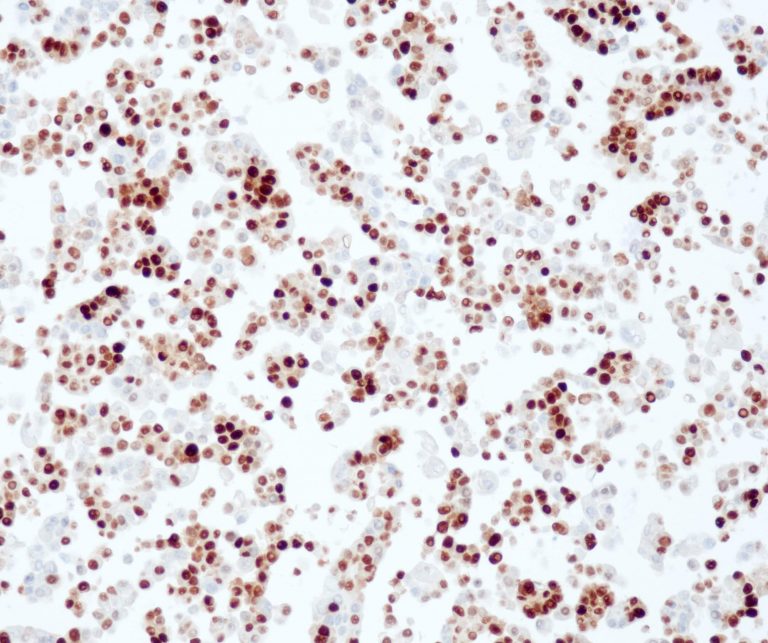

Vascular Pathology

Gastrointestinal (GI) Pathology

General Marker

Breast Pathology

Endocrine Pathology

Gynecological Pathology

Neuropathology

Infection Markers

Lung Pathology

Urinary Tract Pathology

Transplantation Pathology

Soft Tissue Pathology

Hematopathology